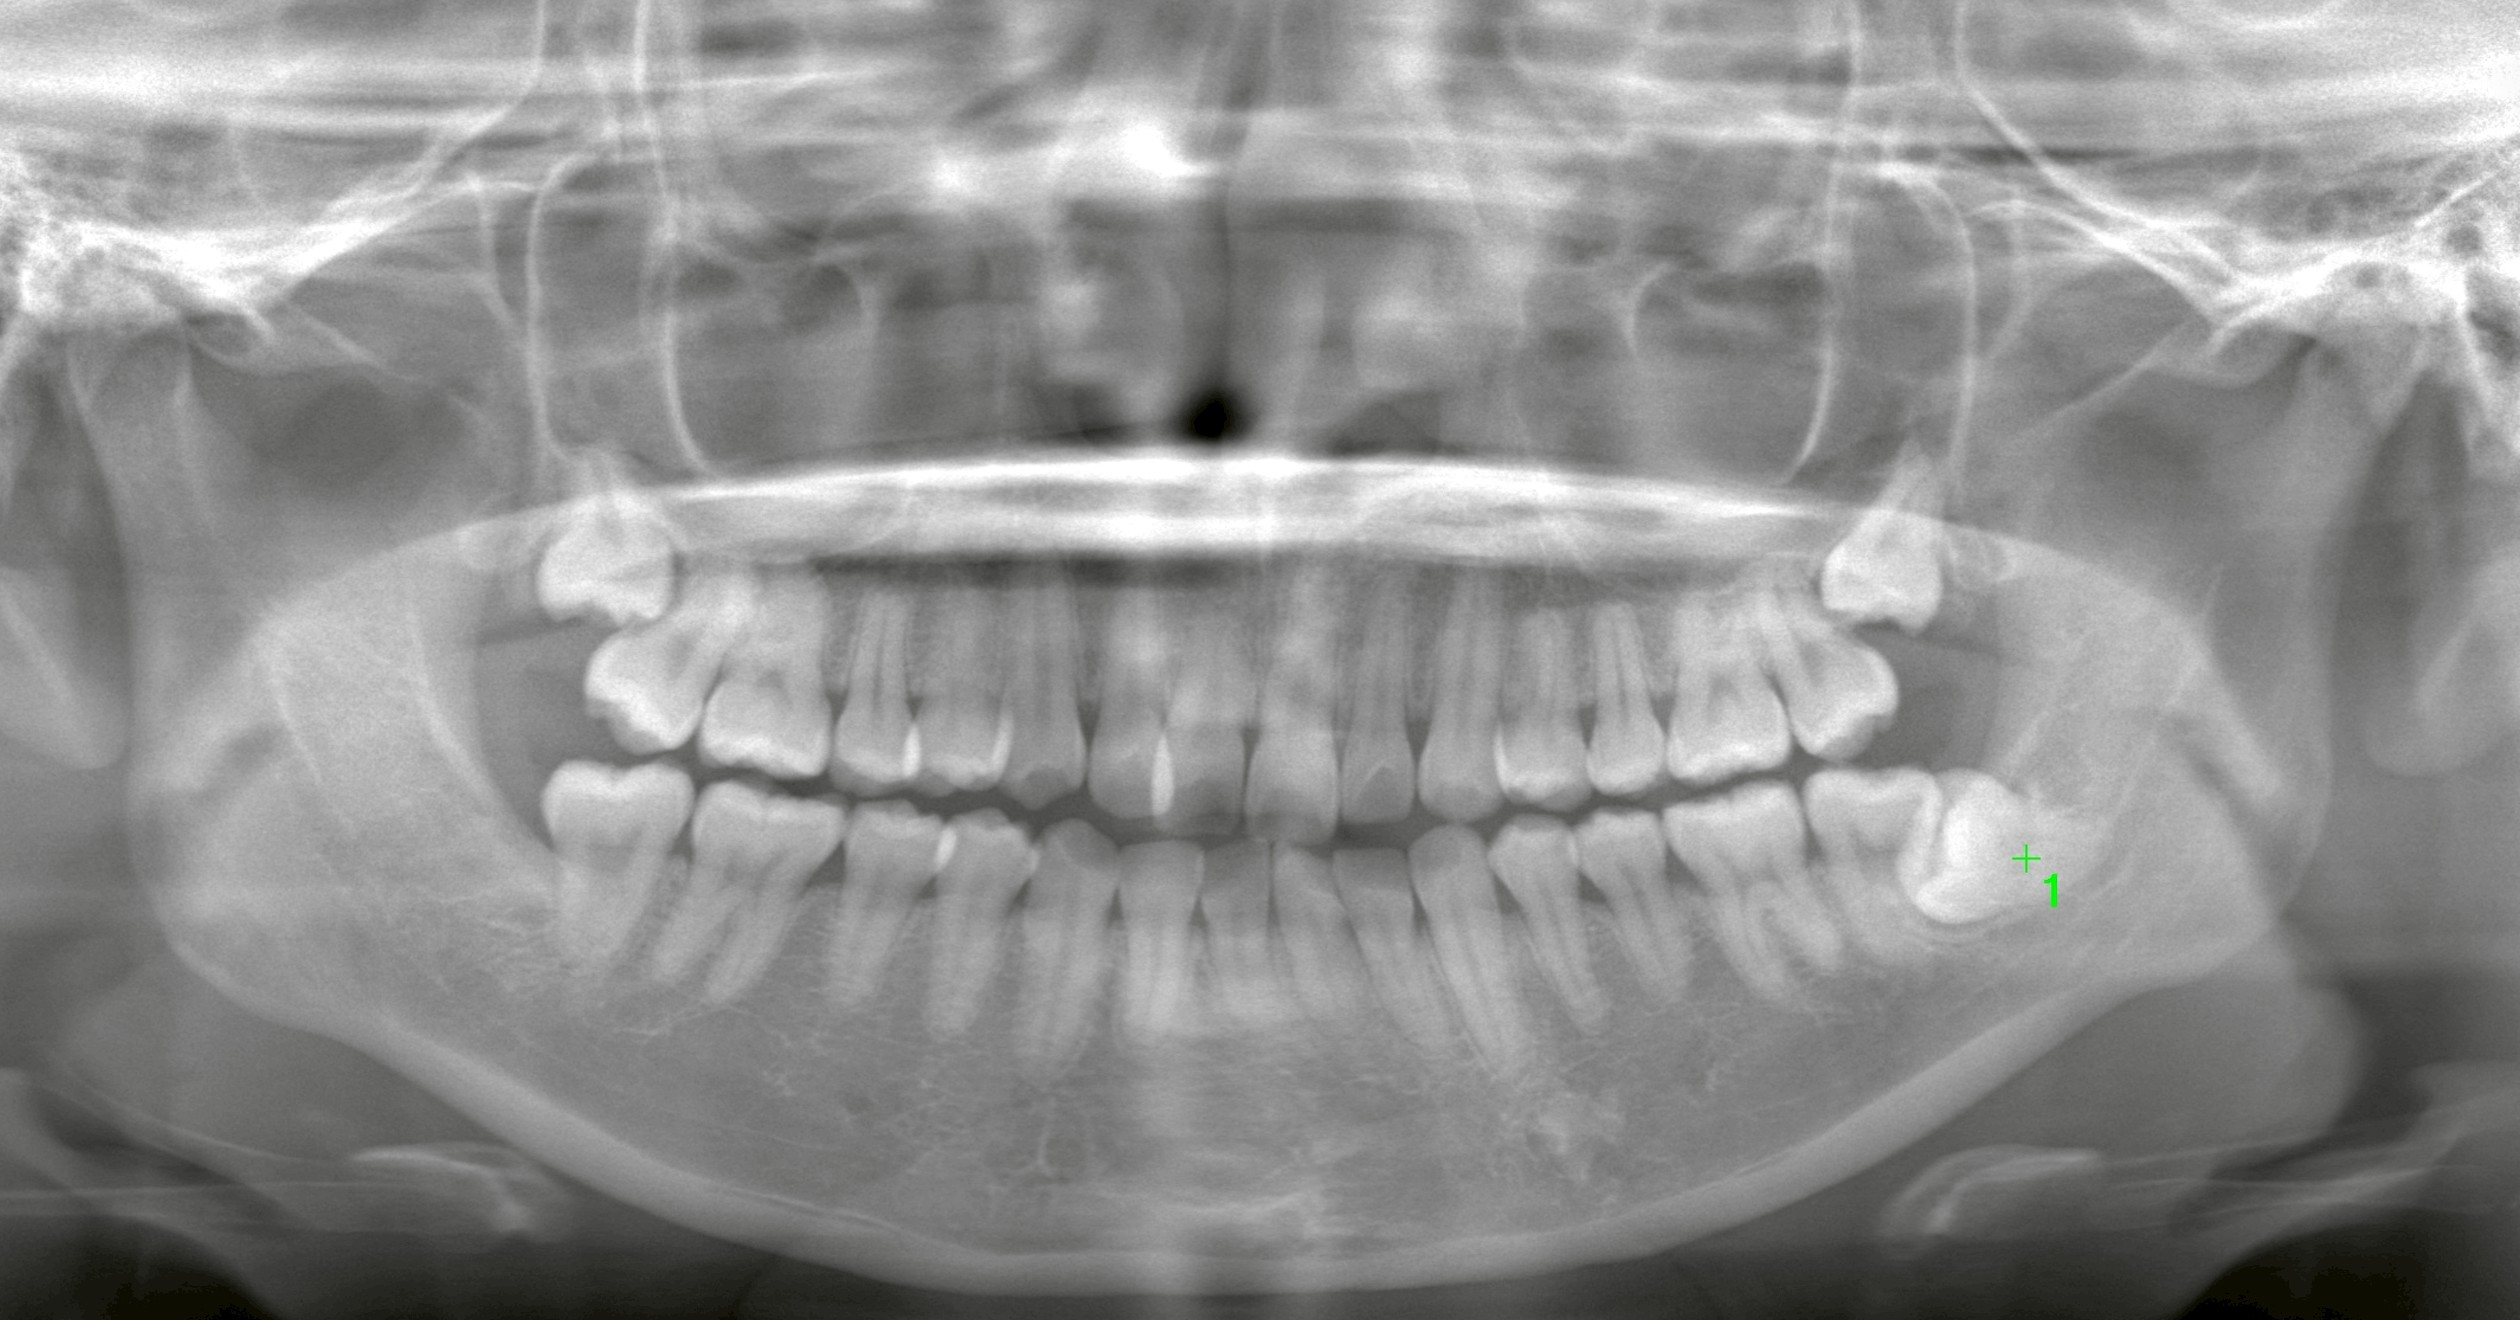

本日の症例:埋伏親知らず3本の同時抜歯

本日は、

* 下顎の埋伏親知らず:1本

* 上顎の埋伏親知らず:2本

計3本の抜歯を同日に実施しました。

すべて歯肉切開・フラップ形成を伴う抜歯でしたが、

CTによる事前評価と、必要最小限の操作を徹底することで、

低侵襲(身体への負担を抑えた)手技で対応しています。